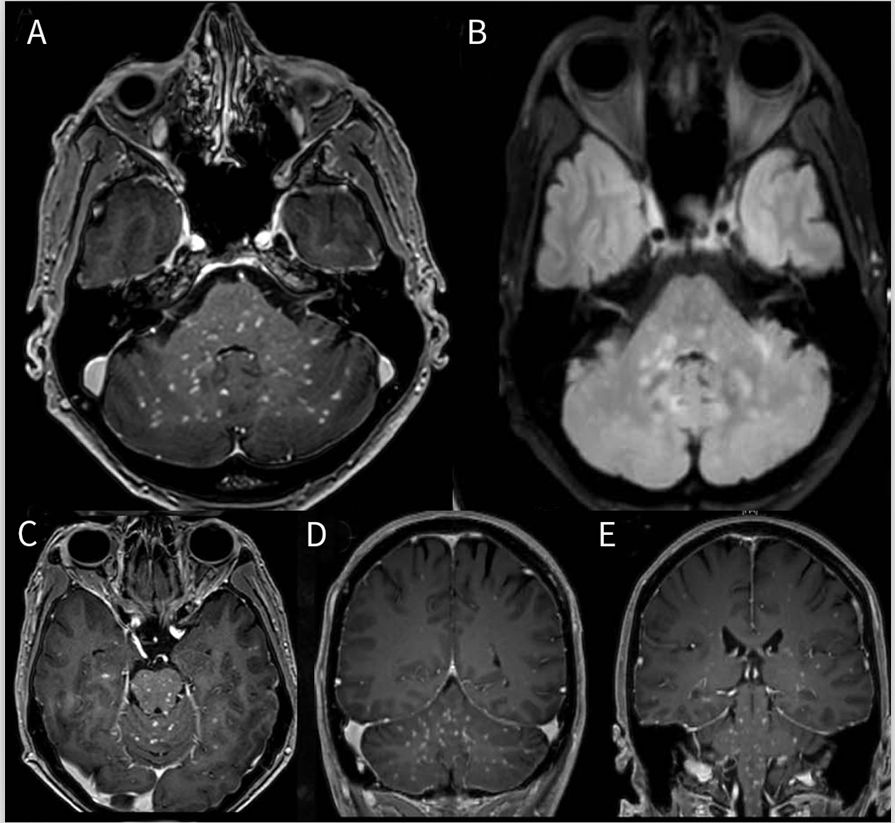

脑干受累,单独或与半球或脊髓疾病相结合,是NBD中最常见的实质表现。神经系统表现通常与诸如口腔溃疡、皮肤病变和发烧等有关。没有口腔溃疡病史的NBD极为罕见。急性发作期间最常见的MRI表现是孤立的、大的、不对称的、汇合的脑干上部病变(图3,C和D),其可能延伸到基底神经节区并横穿间脑。与MS相反,NBD病灶边缘模糊,并呈锯齿状;病灶常伴有水肿和增强,在缓解期间会消退或消失,很少表现为占位病变。脑干、基底神经节和内囊的边缘不清的病灶是较不常见的表现。弥漫性半球高信号病变也可见,常涉及脑室周围和皮质下深部白质。既往研究显示较在NBD急性期,ADC上的信号增加,即弥散增加,但也可在病灶中心看到小范围的弥散受限,提示坏死(图3,A和B),慢性过程会变成黑洞。在慢性或进展性病程中,脑干萎缩可能较明显,但仅在急性发作后12个月或更长时间的少数患者中可见。有学者提出脑干萎缩更支持NBD(相对于MS),尤其是在没有皮质萎缩的情况下。

NBD的原发性出血与脑静脉窦血栓形成或颅内动脉瘤无关,并不常见。既往研究显示8%的NBD患者发生脑出血。最近使用的磁敏感加权成像(SWI)的研究显示在84%的病灶中显示出与出血一致的信号变化。另一项研究显示75%的进展性NBD会出现黑洞。

图3 神经白塞病患者的MRI影像。弥散加权(A)成像和表观弥散系数(B)序列显示左侧内囊后肢中央弥散受限病灶。T2加权冠状位(C)和轴位(D)显示大的不对称性脑干右侧病灶延伸到小脑白质(箭头)。

神经结节病

结节病是一种肉芽肿性疾病,全身变化包括经常偶然发现的肺部表现、葡萄膜炎和结节性红斑。估计至少有5%–10%的结节病患者会发生神经结节病(NS)。大约20%的病例会发生脑干或小脑综合征。

MRI可表现表为脑膜、下丘脑-漏斗状和颅神经等受累,或脑积水、实质和硬脑膜占位病变(图4)。颅底或广泛的软脑膜增强是NS的特征性表现。增强模式可为弥漫性、结节状或沿血管周围空间扩散。NS脑干病灶的形态为非特异性,如果存在实质病灶时可出现增强,并常伴软脑膜强化。这种典型的“由外而内”的外观强烈支持NS。硬脑膜的不连续增强和T2低信号认为是区分位于后颅窝轴外肉芽肿样占位与脑膜瘤等肿瘤的特征。尽管颅底周围血管存在炎症,但脑干梗死还是罕见。当脑干改变与纵向广泛性脊髓炎同时发生,脊柱背侧强化提示NS。CSF蛋白水平中度升高(> 1g/L),且通常无寡克隆带可能有助于NS与MS的鉴别诊断。CSF血管紧张素-转化酶(ACE)的水平既不特异也不敏感。

图4 神经结节病患者的MRI影像。轴位T1增强(A,C)和FLAIR序列(B),冠状位T1增强(D,E)显示整个脑干点线状病变并延伸到小脑脚和白质,所有病灶在T 1增强上比T2或FLAIR序列更明显。